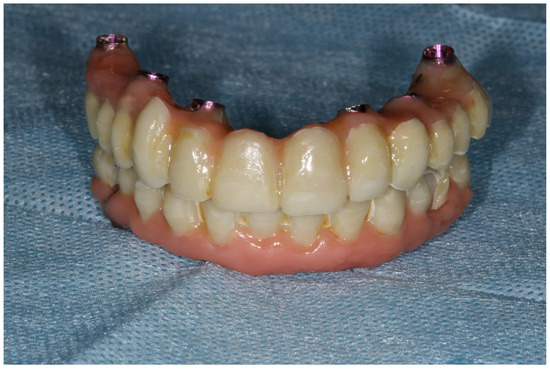

- One-day surgery with implant placement, MUA, and intraoral welding to obtain immediately loaded long-lasting temporaries.

- The conduction of a Sheffield passive fit test of 3D-printed try-ins on a milled titanium bar.

- Final restoration delivery with occlusal equilibration.